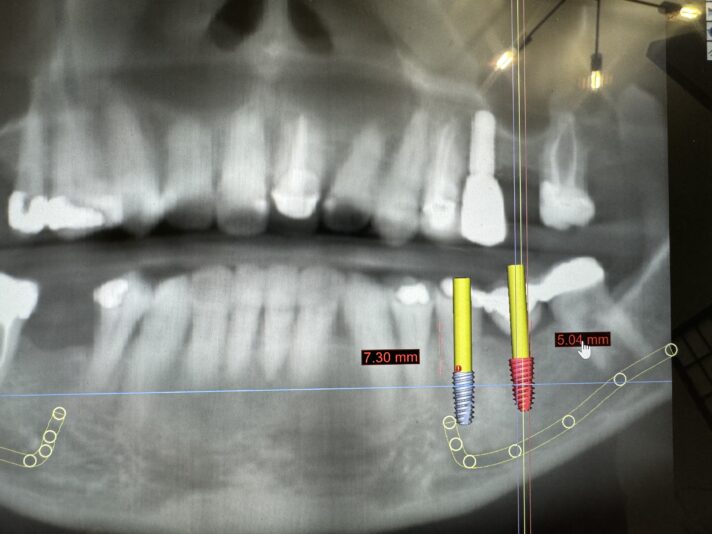

#20 is planned for an extraction. Patient wants to know fixed options so my thought is bridge #20-x-x-18 (not the greatest option due to bone loss on both abutment teeth) or implant #20 and #19. The ridge width around #20 is naturally narrow (6.5-7mm – virtual implant I placed Is 3.5×8.5mm). #20 also has 4mm buccal recession/dehiscence…